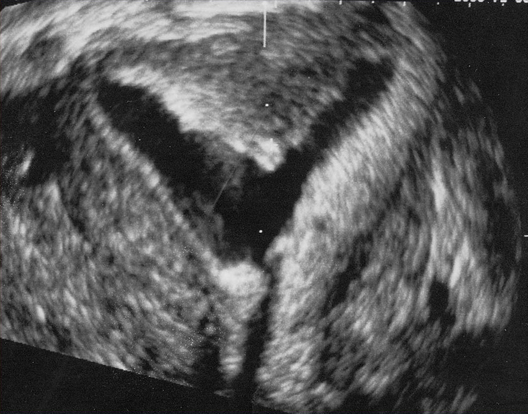

Myomètre en écho 3D. Hystérosonographie. Permet d’obtenir une coupe frontale de l’utérus. Pas d’intérêt en routine